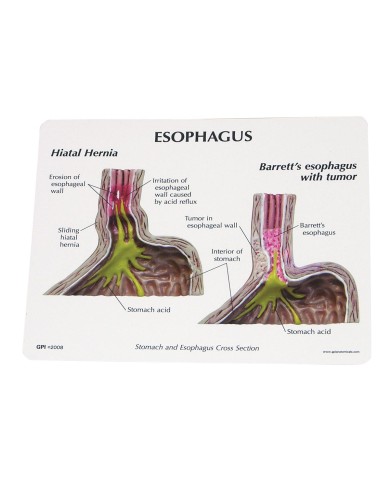

Questo e tanto altro ancora trovi nella sezione dedicata ai modellini anatomici, occhi, denti, orecchio, naso e gola, e i modelli anatomici per ostetricia e ginecologia, per lo studio dell'anatomia della pelvi e del bacino umano.

I modelli anatomici didattici sono riproduzioni di strutture anatomiche perfettamente uguali a quelle vere, i modelli di ossa sono realizzati dalla scansione di ossa vere, l'esperienza tattile è assolutamente realistica, ed anche il peso delle ossa corrisponde all'incirca al peso delle ossa vere.

Gli studenti di medicina utilizzano i modelli anatomici per i loro studi di anatomia umana, studiare l'anatomia sui libri non basta, un modellino anatomico permette uno studio molto più accurato che una foto o un disegno su un libro.

Medici, fisioterapisti, osteopati e professionisti sanitari utilizzano i modelli anatomici per dare spiegazioni ai pazienti sulle patologie, risparmiando tanto tempo prezioso durante la spiegazione, che diventa molto più efficace.